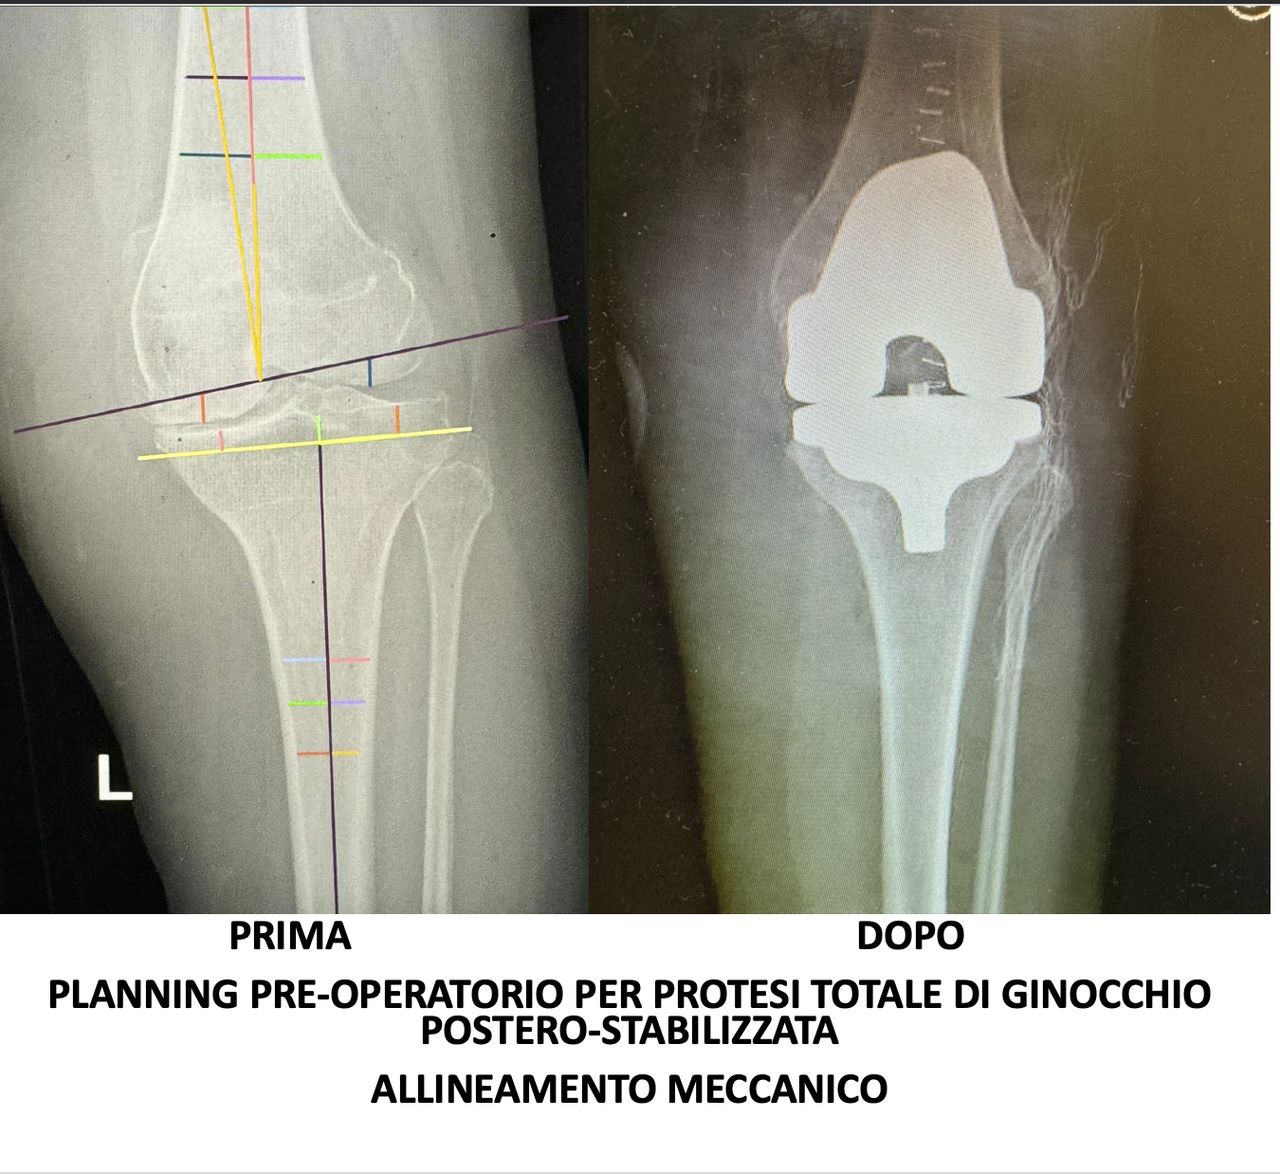

Nel 2018 frequenta come “Academic Observator” l’U.O. di Ortopedia “CDC Sileno e Anna Rizzola” di San Donà di Piave dedicandosi alla protesica di ginocchio con protocollo “fast-track”, pubblicando articolo su rivista internazionale intitolato “Experience-optimised fast track improves outcomes and decreases complications in total knee arthroplasty”.

Svolge la sua attività presso l’Ospedale del Mare, occupandosi di chirurgia traumatologica, con predilezione alla protesica di ginocchio e medicina rigenerativa della cartilagine articolare.

• Ortopedia del ginocchio